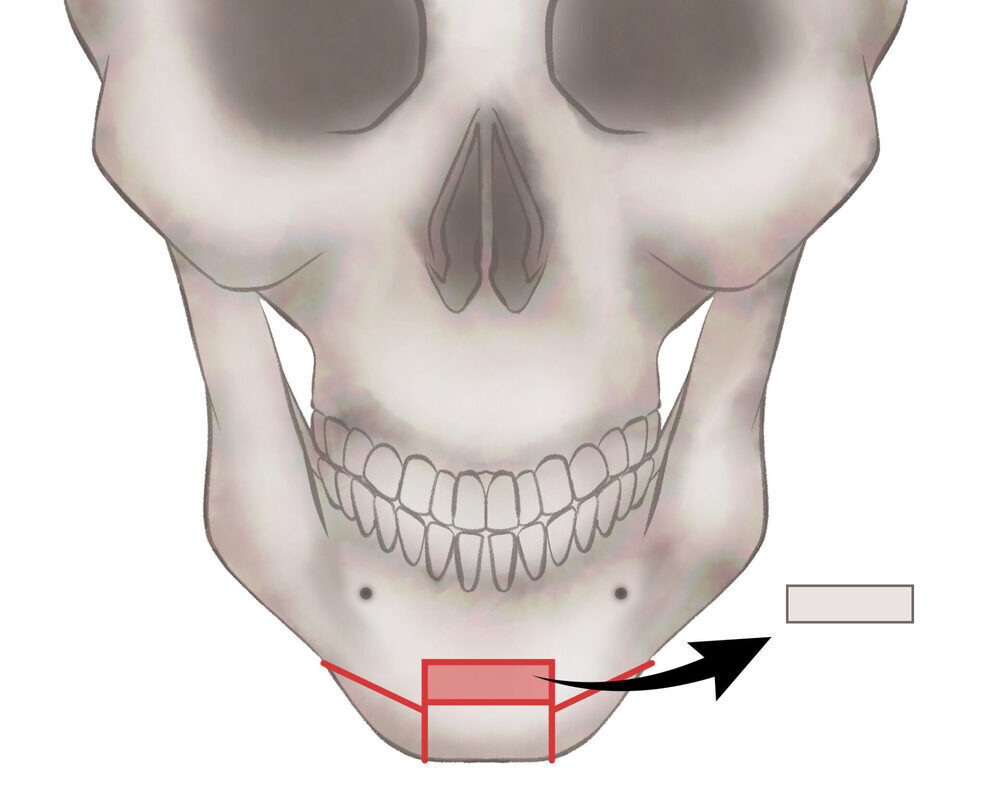

オトガイ骨切り(中抜き)

1.切開線をデザインします

2.骨を切除します

3.骨を移動させ段差を削ります

4.プレートで固定します